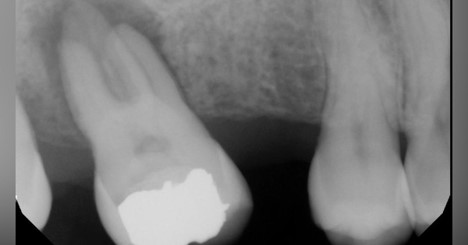

Which restorative material is MOST appropriate for this extensive cavity preparation?

Which material is NOT recommended for lining this cavity before placing a composite restoration?

What does the radiograph show, indicating a potential need for root canal treatment?

Which restorative material is depicted in the image?

What is the MOST likely diagnosis based on the radiographic findings?

What is the MOST likely indication for using the restorative material seen in the imag